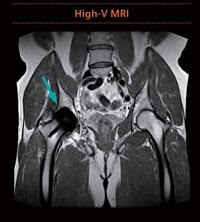

インプラントイメージング

人口統計の変化に伴い、金属インプラントを挿入した被検者のMRI 検査はますます増加している。MAGNETOM Free.Star の新しい磁場強度0.55 テスラは金属アーチファクトの低減につながるため、インプラントイメージングにも有用である。

ルーチン検査においても高画質と撮像時間の短縮※を実現し、信頼性の高い診断に貢献する。

左:従来の MRI による金属インプラント画像

右:High-V MRI による金属インプラント画像